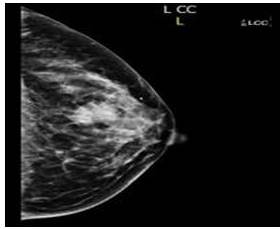

En mamografía izquierda se evidencia lesión irregular, de contorno espiculado con calcificaciones dispersas en UCS de mama izquierda, BIRADS 4C y la biopsia con aguja gruesa reporta: carcinoma ductal infiltrante bien diferenciado, estudios de extensión sin alteraciones. Se decide llevar a mesa operatoria para mastectomía parcial oncológica (MPO) con corte congelado (CC) y ganglio centinela (GC) con azul patente.

En la mamografía, los MpBC muestran muchas similitudes con el IDC, En el caso actual, la paciente presentó lesión de crecimiento acelerado, en cuya mamografía se evidencia imagen espiculada con calcificaciones sugestivas de malignidad en UCS de mama izquierda, sin adenopatías axilares (Figura 5 y 6).